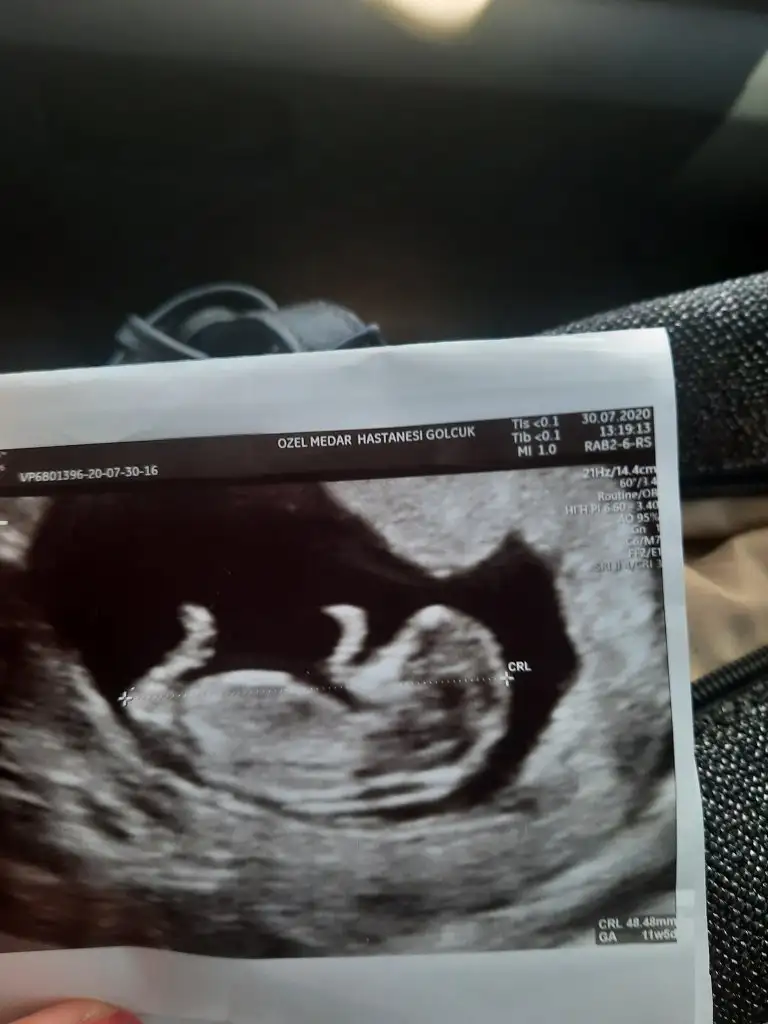

Erkek gibiMerhaba herkese Ikra meyra bebegimin ultrosan fototsunu attim banada yorum yapabilir misin lutfen 11+3

Net değil olursa 12-13 hafta tekrar paylaşınSelam arkadaşlar, biz de bugün 11+4 olduk. Cinsiyet tahmini alabilir miyiz ☺